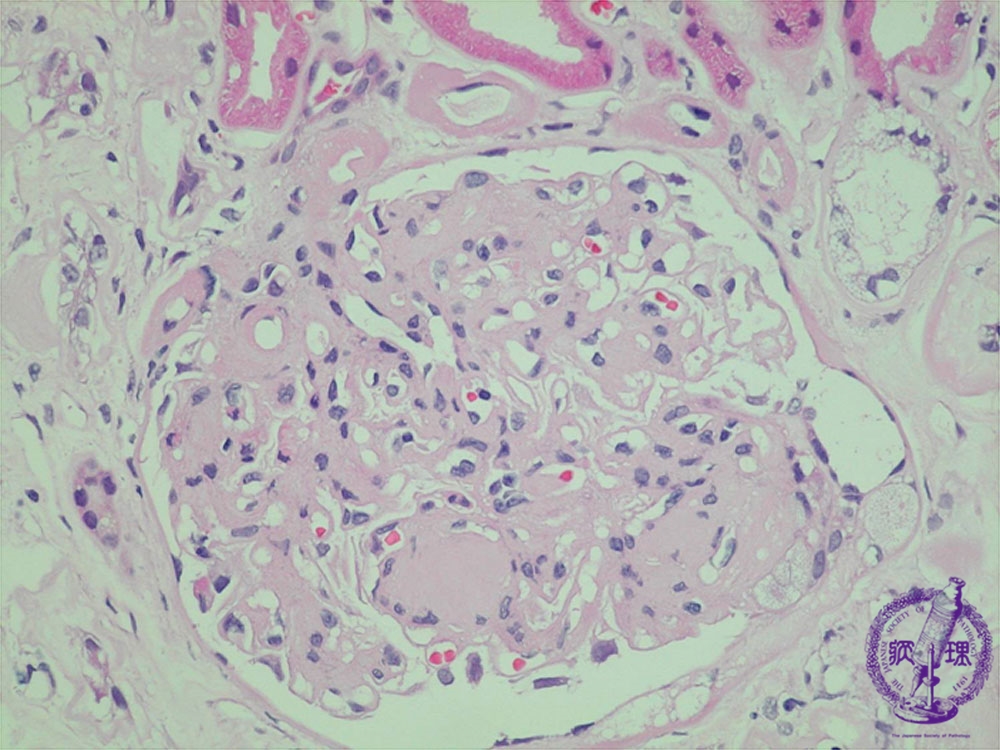

- (7)Diabetic nephropathy

Microscopic findings (HE, high power view): Nodular lesion. Eosinophilic material forms nodular deposits (yellow dotted line) within the mesangium pushing mesangial cells to the periphery, the quintesessential finding in diabetic nephropathy. There is arteriolosclerosis demonstrated by marked hyalinization in the walls of afferent and efferent arteries and arterioles. (yellow arrows).